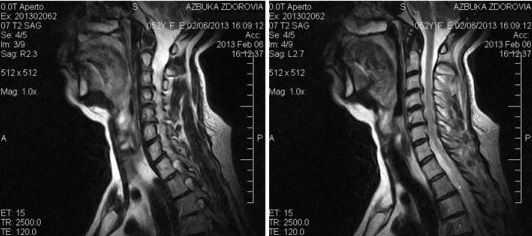

Показания и противопоказания к томографии шейного отдела

МРТ шеи: перелом зубовидного отростка, миелопатия (дисфункция спинного мозга в области поврежденных шейных позвонков) в коронарной плоскости (Т2 последовательность, STIR)

Показаниями к проведению МРТ шейного отдела позвоночника служат:

МРТ шеи: миелопатия (аксиальная плоскость, Т2 ВИ)